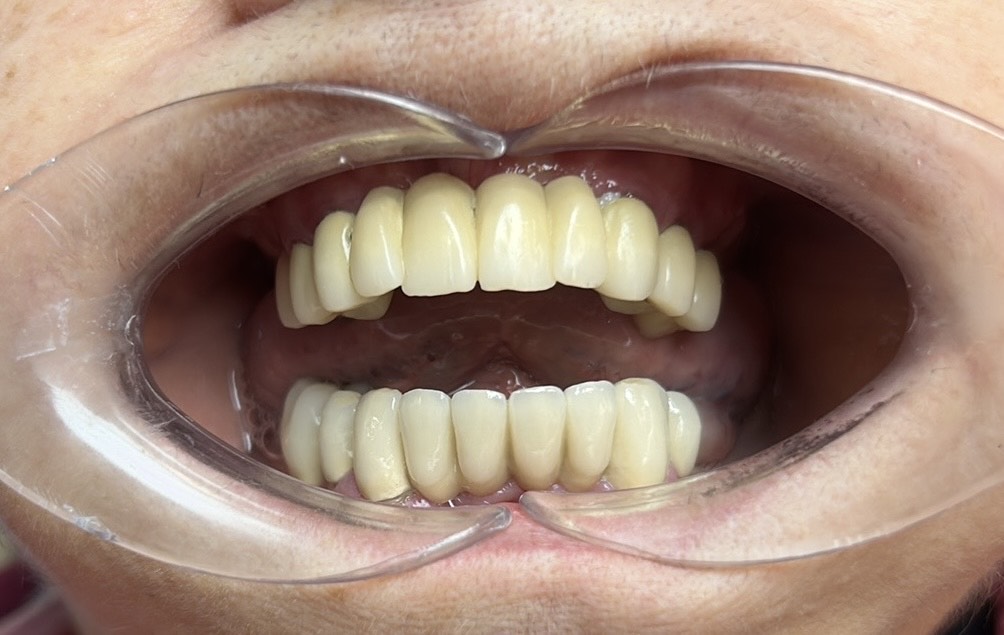

Előtte-utána: Régi alsó fémkerámia körhíd cseréje